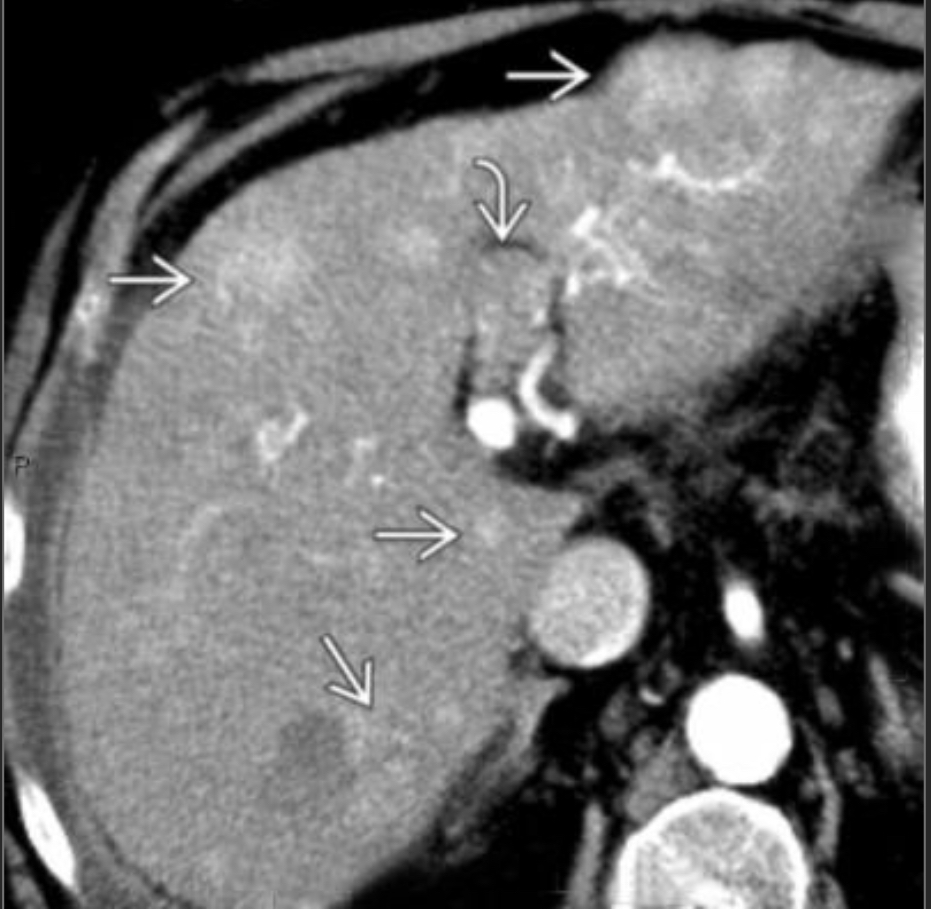

54m w/cirrhosis 2/2 alcohol

Arterial phase CECT w/multiple hyperdense/hypervascular foci c/w tumor (these wash out on PV phase where the tumor thrombus is also more apparent) we also see cirrhosis w/small nodular border

Criteria to distinguish portal vein tumor thrombus (vs. bland thrombus) are contiguity with parenchymal tumor, expansion of the lumen of the vein, and enhancing thrombus.